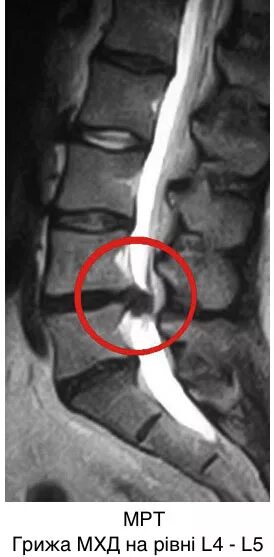

Грыжа с3